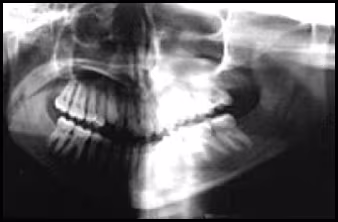

These figures demonstrate the effects of twisting. Elongation of left mandible, reduction in size of teeth on the opposite side, occlusal plane canting and pronounced tooth overlap on the same side.

Figure 43A. Panoramic Image.

Figure 43B. Panoramic Schematic.